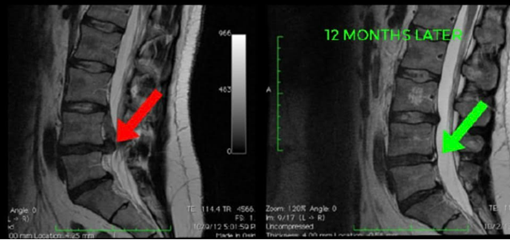

Low Back Pain Physiotherapy Melbourne - Lower back pain is one of the most common causes of pain & disability with up to 80% of people experiencing lower back

Successful physio for a pinched nerve in the lower back involves 3 aspects: Symptom reduction, Activity modification & lower back, pelvic and hip strengthening